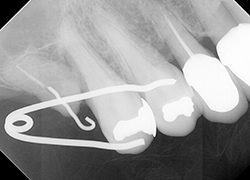

【治療中】

特殊な部分矯正装置を用いて、アップライト(引き起こし)を試みました。

【治療後】

無事引き起こすことが出来ました。治療期間は約2ヶ月です。